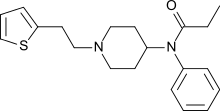

Anilidopiperidines

Phenylpiperidines

The first fully synthetic opioid was meperidine (later demerol), found serendipitously by German chemist Otto Eisleb (or Eislib) at IG Farben in 1932.[228] Meperidine was the first opiate to have a structure unrelated to morphine, but with opiate-like properties.[199] Its analgesic effects were discovered by Otto Schaumann in 1939.[228] Gustav Ehrhart and Max Bockmühl, also at IG Farben, built on the work of Eisleb and Schaumann. They developed "Hoechst 10820" (later methadone) around 1937.[230] In 1959 the Belgian physician Paul Janssen developed fentanyl, a synthetic drug with 30 to 50 times the potency of heroin.[211][231] Nearly 150 synthetic opioids are now known.[228]